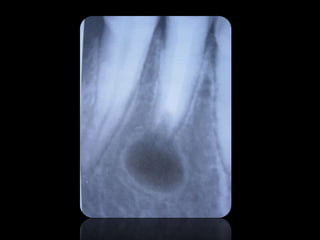

ABSCESO PERIAPICAL

QUISTES